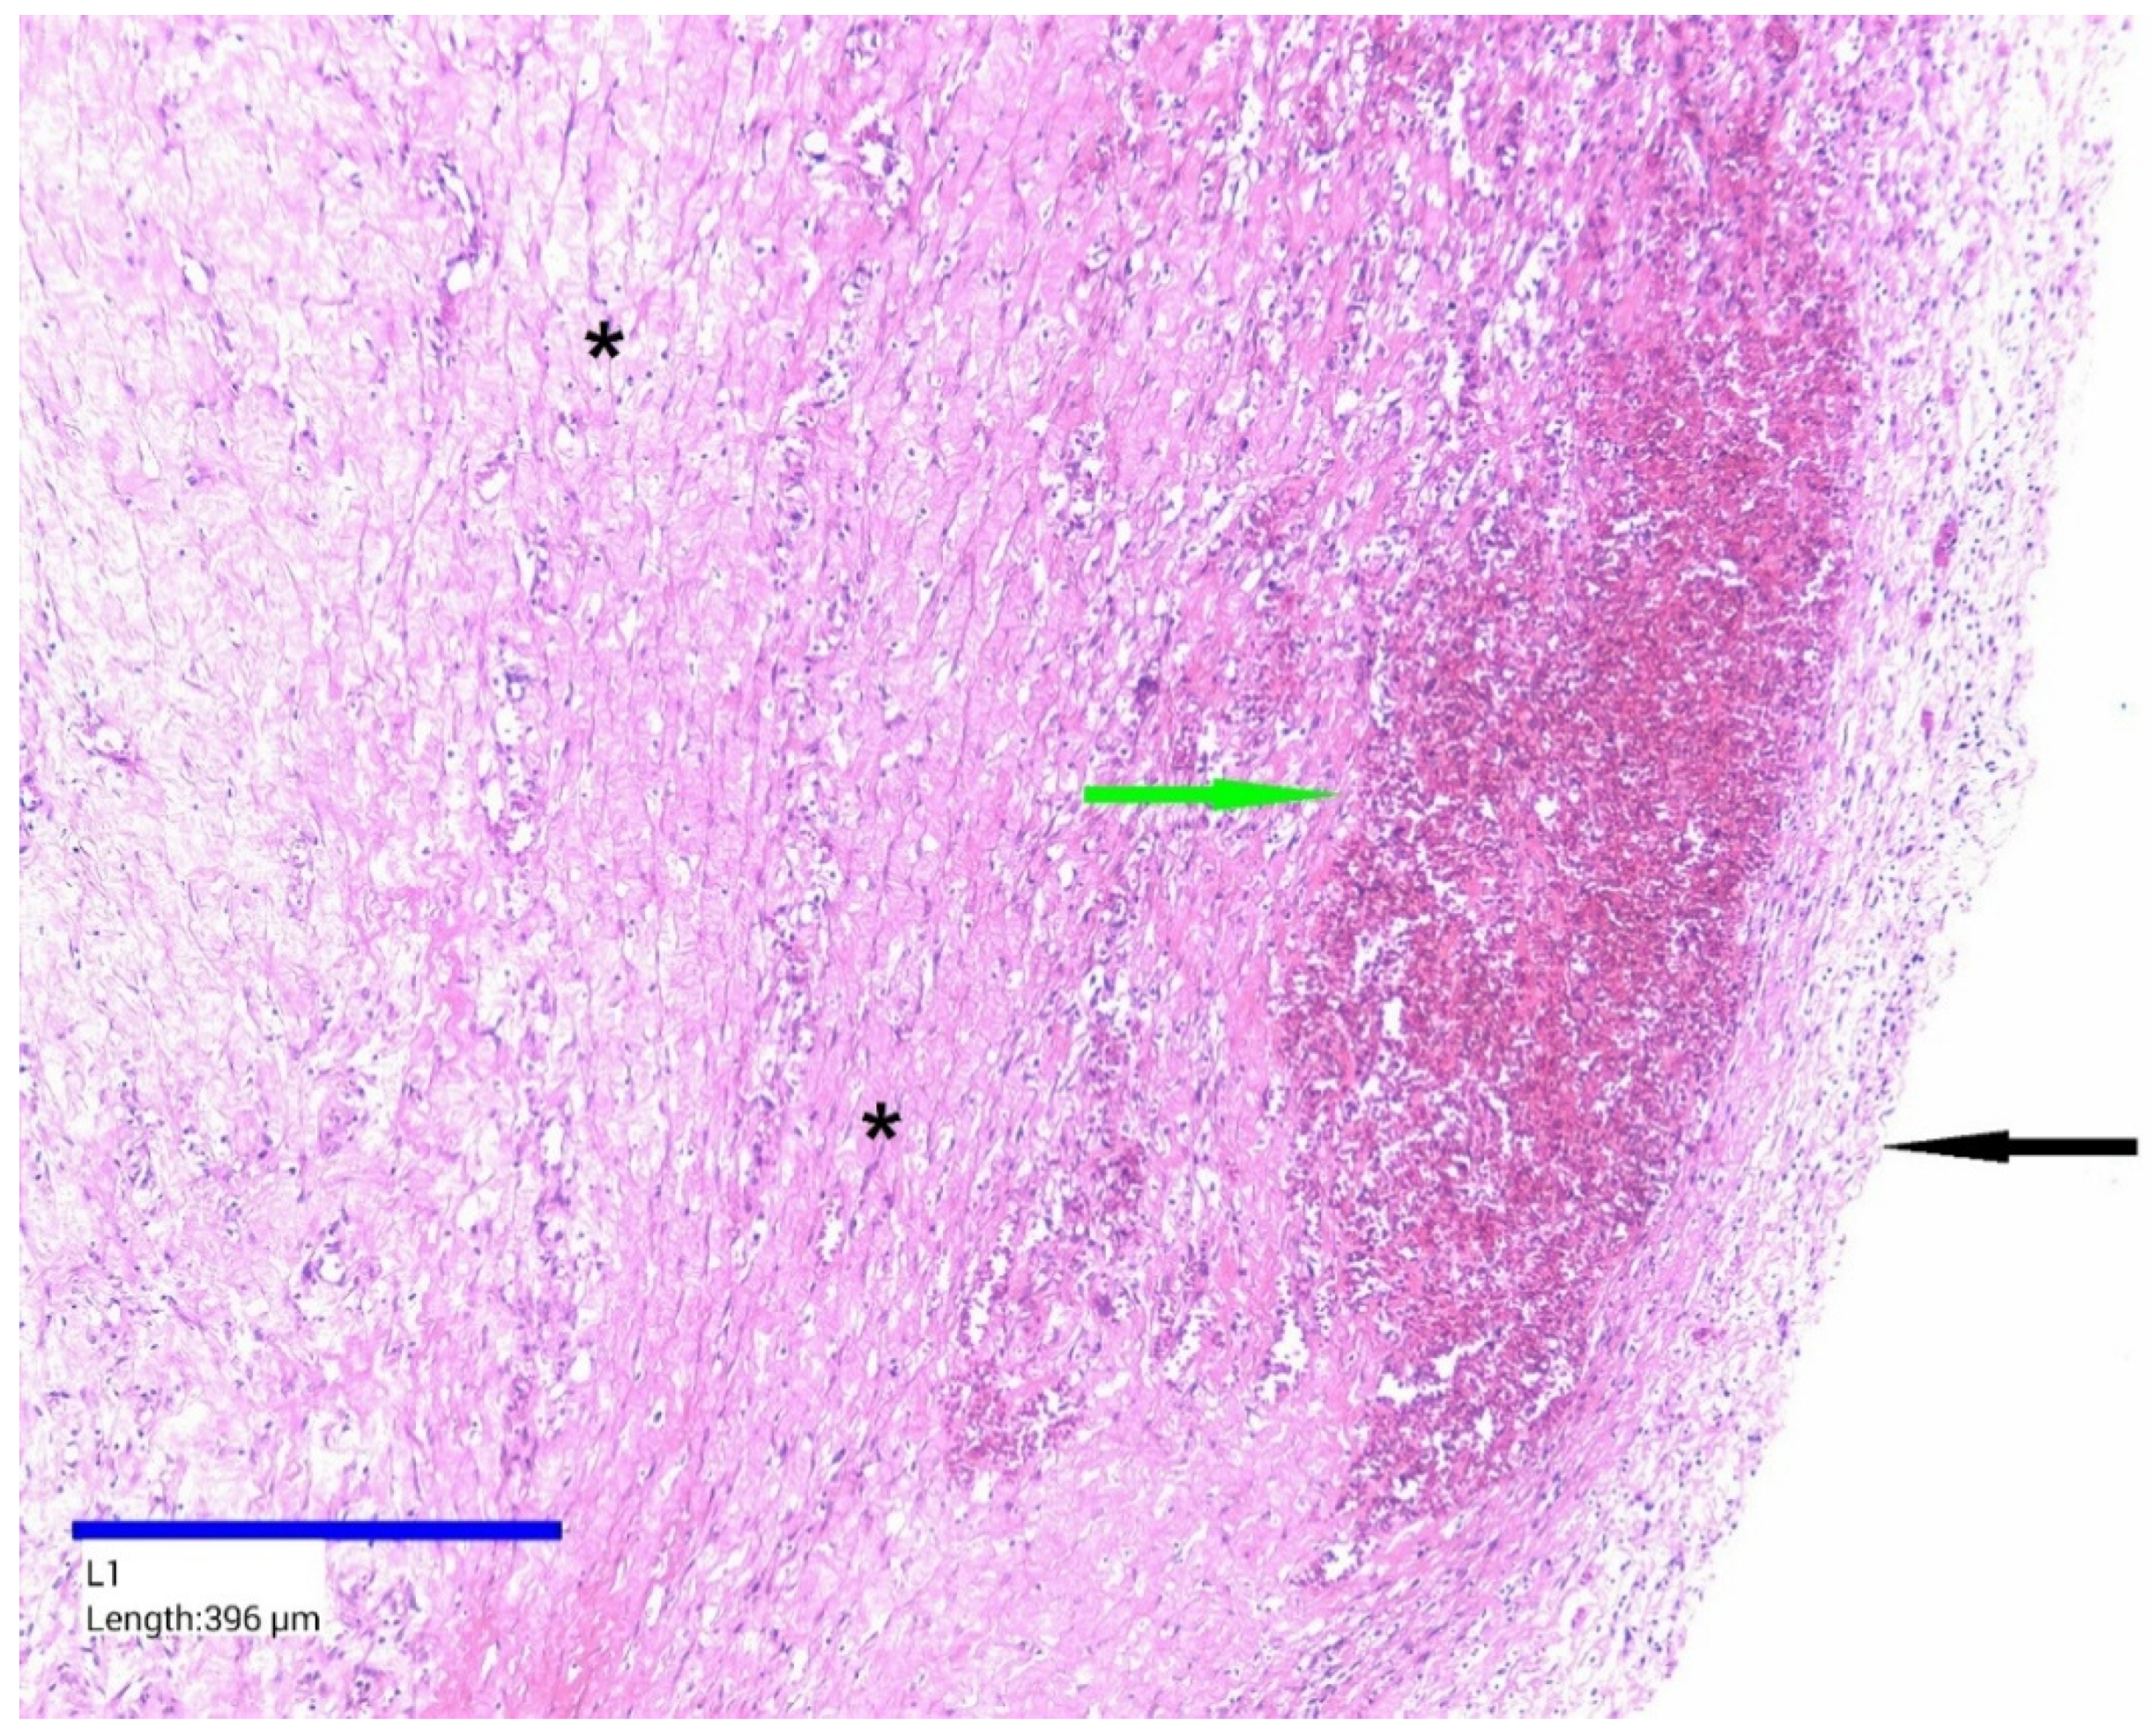

2. Case Presentation